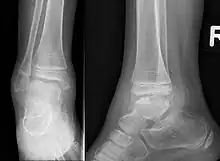

Trevor disease in a nine-year-old girl: talus

3D CT image of Trevor's disease of the ankle and talus.

This disorder is rare, and is characterised by an asymmetrical limb deformity due to localized overgrowth of cartilage, histologically resembling osteochondroma. It is believed to affect the limb bud in early fetal life. The condition occurs mostly in the ankle or knee region and it is always confined to a single limb. This usually involves only the lower extremities and on medial side of the epiphysis. It is named after researcher David Trevor.[1]

Trevor disease was first described by the French surgeon Albert Mouchet and J. Belot in 1926. In 1956, the name "dysplasia epiphysealis hemimelica" was proposed by Fairbank.[1] The usual symptoms are the appearance of an osseous protuberance, on one side of the knee, ankle or foot joint which gradually increases Radiologically,[14] the condition shows a nonuniformity of growth and multiple unconnected ossification centers around the epiphyses.[8]